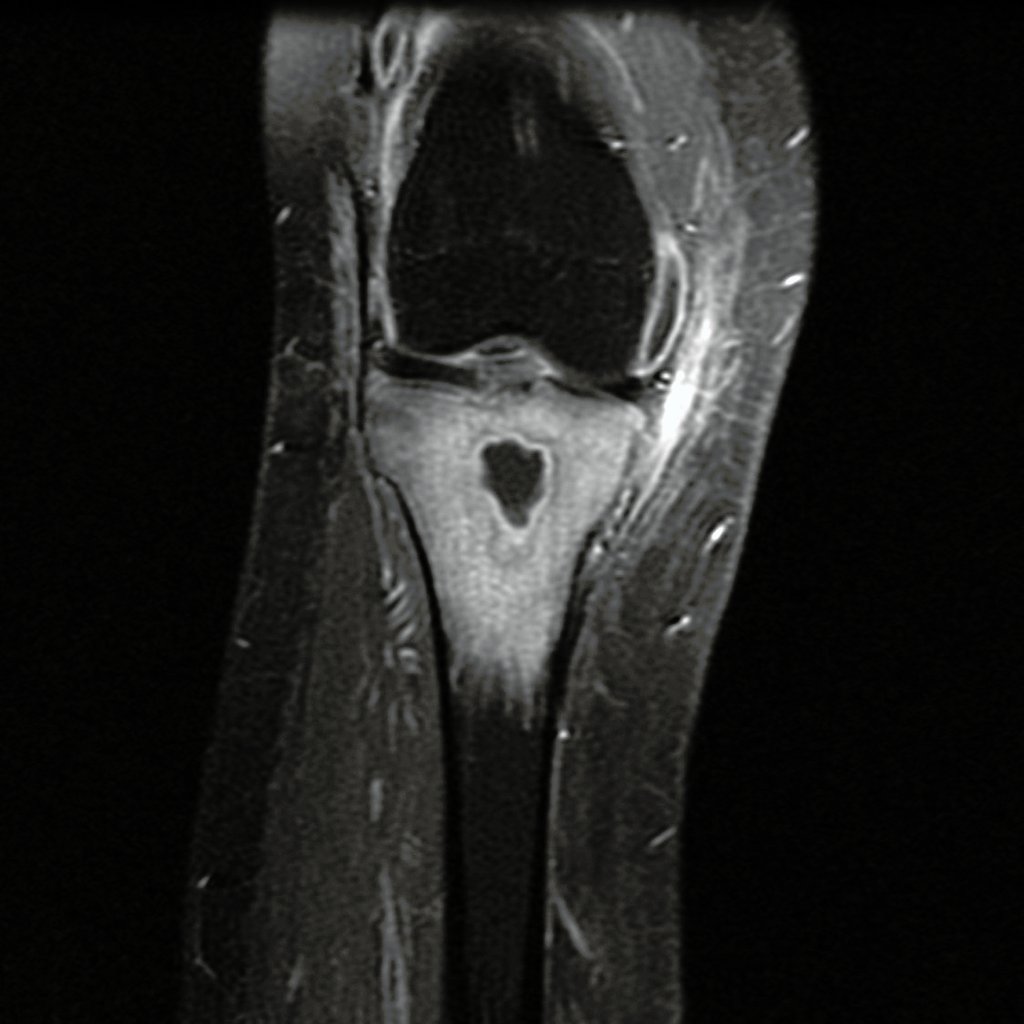

(OSTEOMYELITIS) is a serious condition in which bone gets infected.

Infection could be due to bacteria or fungus.